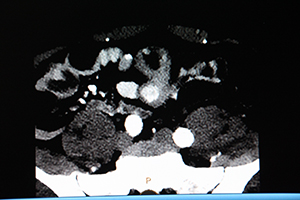

神経内分泌腫瘍(NET)症例の通常画像。大腸に複数の造影効果が認められる。 |